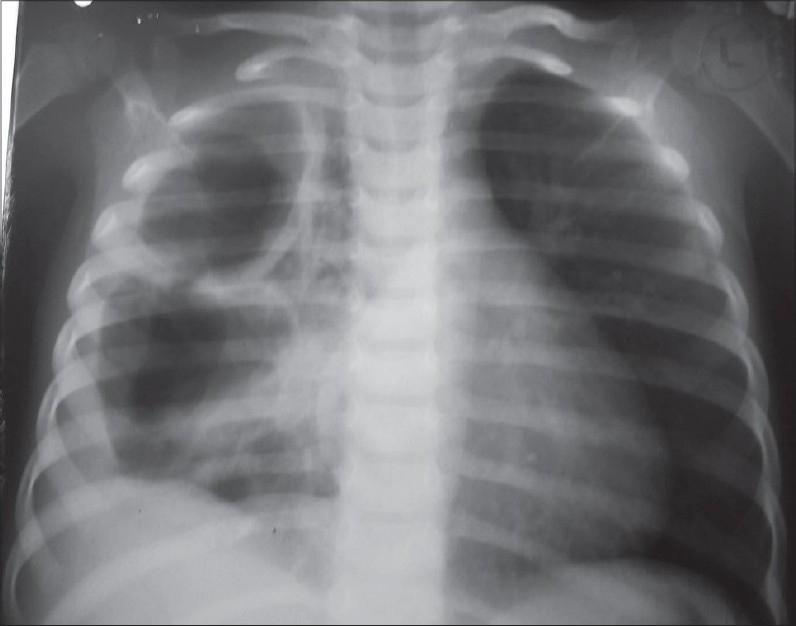

小儿脓胸:手术治疗

Empyema thoracis can produce significant morbidity in children if inadequately treated. Correct evaluation of the stage of the disease, the clinical condition of the child and proper assessment of the response to conservative treatment is crucial in deciding the mode of further surgical intervention. This ranges from intercostal chest tube drainage and video-assisted thoracoscopic surgery to open decortication. Surgical decortication becomes mandatory in neglected cases; it gives very gratifying results ameliorating the disease rapidly and is well tolerated by young patients. This article reviews the current literature and discusses the important considerations while managing these patients. Indications for surgery are highlighted, based on our large experience at a tertiary care center.

如果治疗不当,小儿脓胸可导致严重的发病情况。正确评估疾病阶段、患儿临床状况以及对保守治疗反应的恰当评估,对于决定进一步手术干预方式至关重要。这包括肋间胸腔闭式引流、电视辅助胸腔镜手术以及开胸纤维板剥脱术。在被忽视的病例中,手术纤维板剥脱术成为必要手段;它能迅速改善病情,取得非常令人满意的效果,且年轻患者耐受性良好。本文回顾了当前文献,并讨论了管理这些患者时的重要注意事项。基于我们在三级医疗中心的丰富经验,突出了手术适应症。